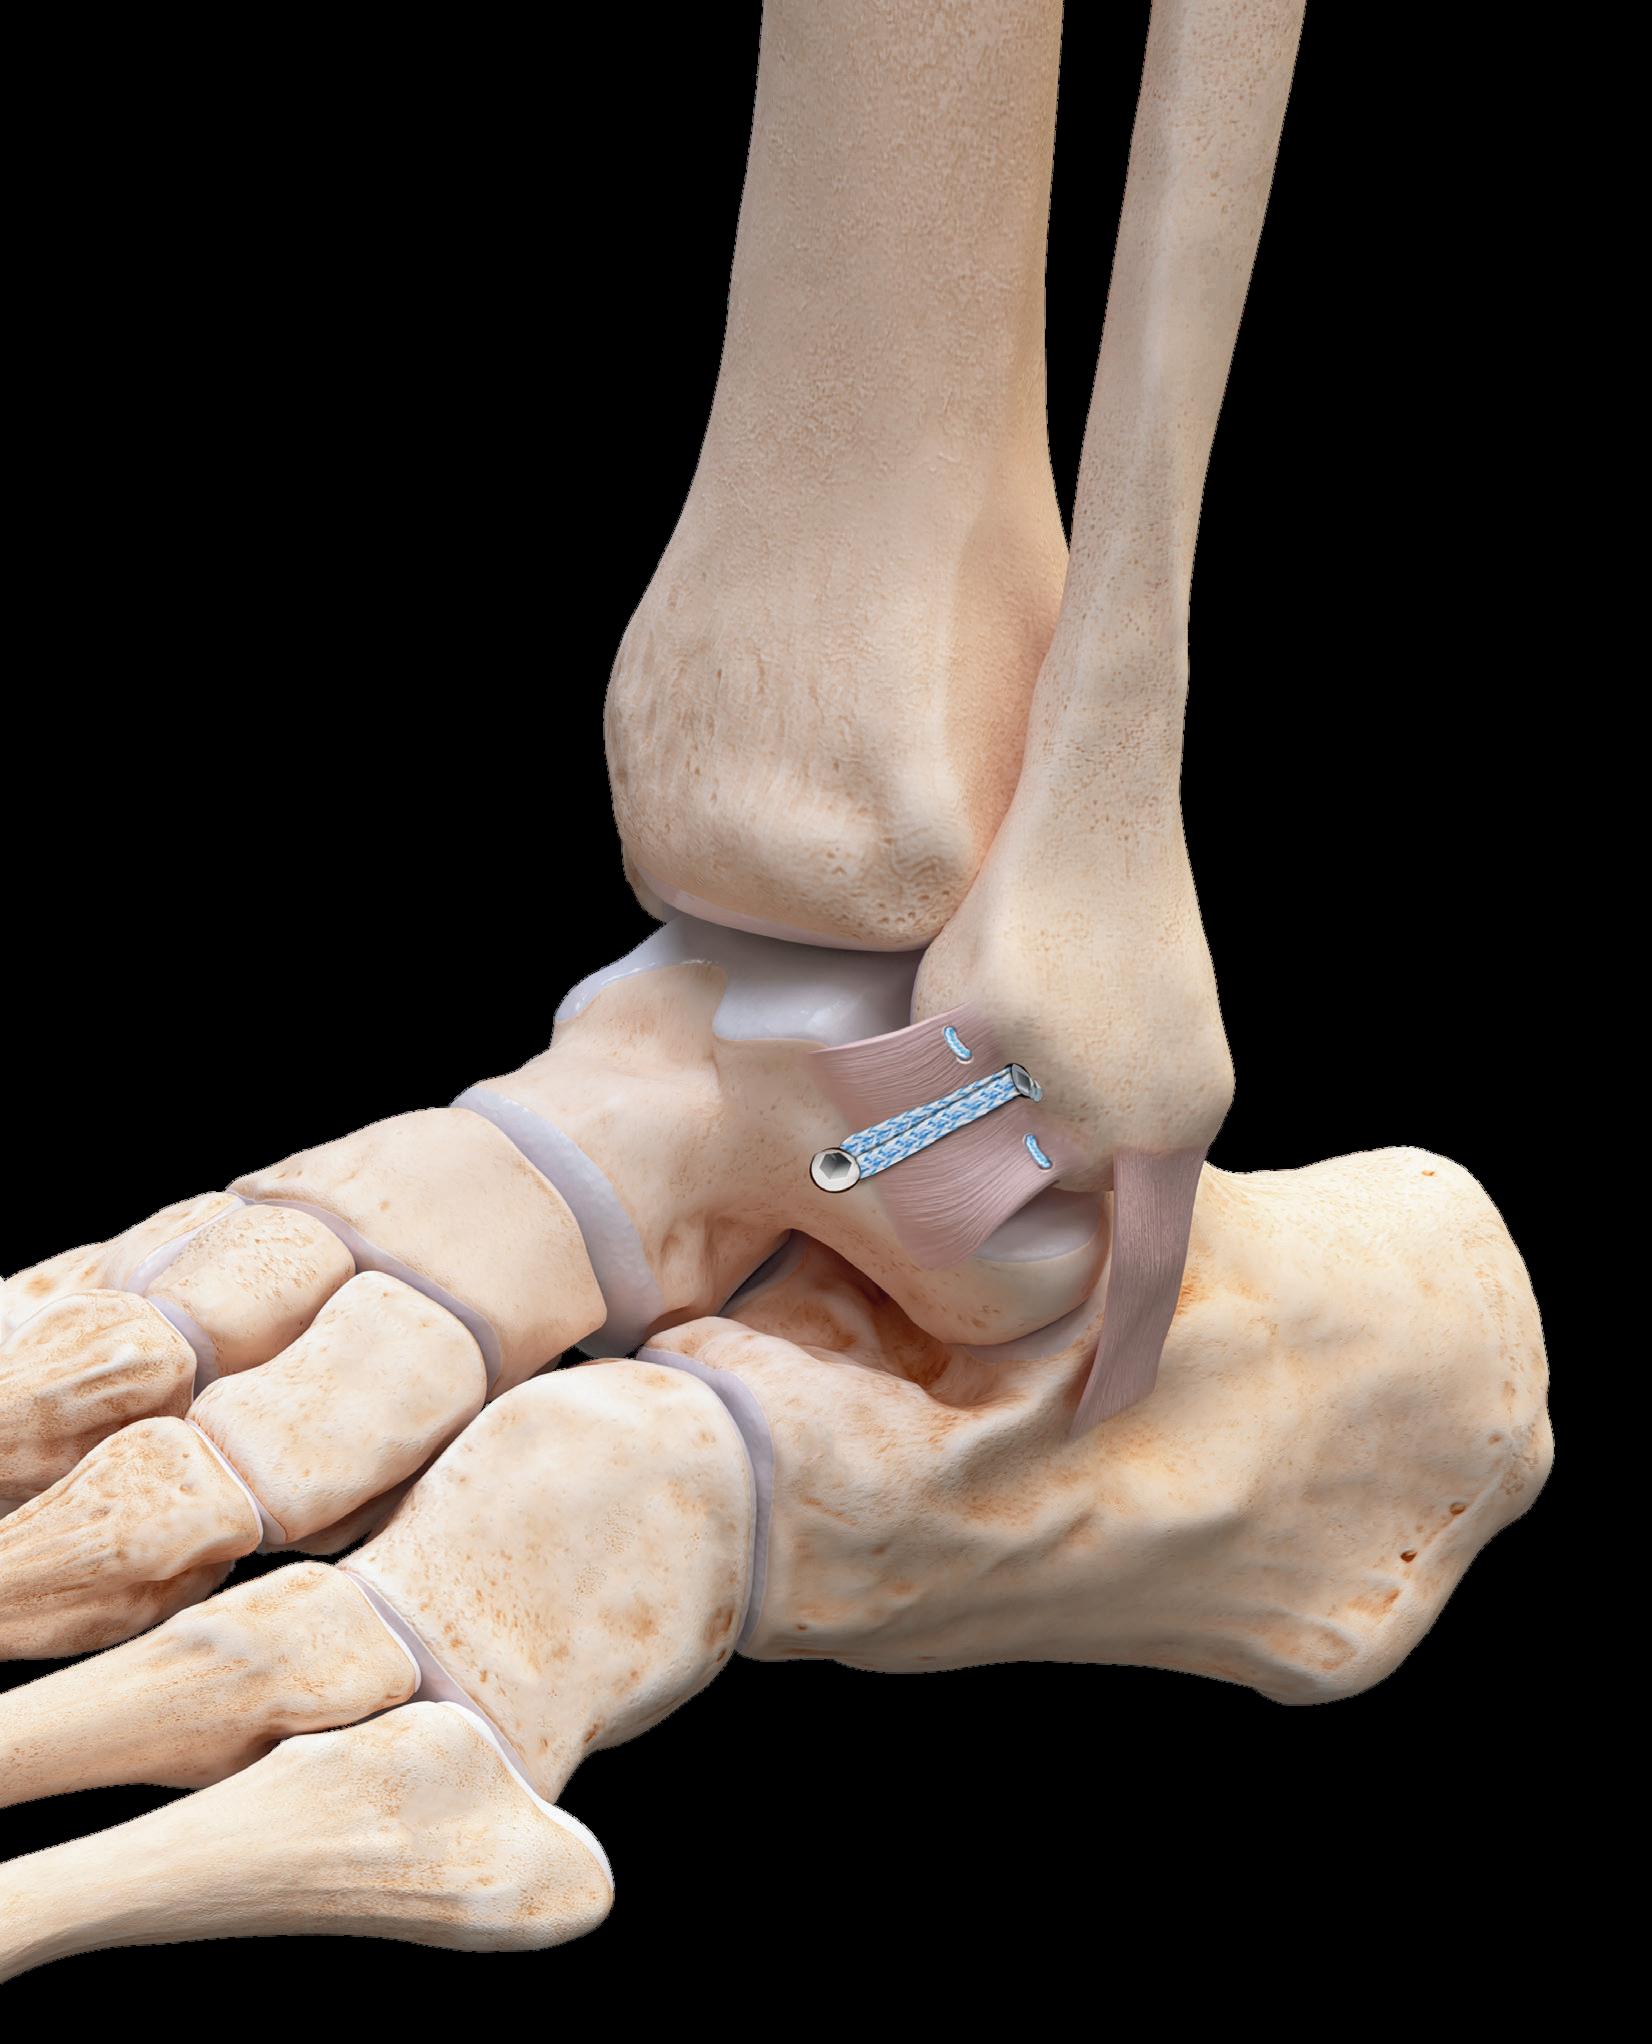

First in market to offer Adjustable Tensioning Technology* for insertional Achilles reconstruction and lateral ankle instability repair

Smith+Nephew, the global medical technology company, today announces the launch of a comprehensive foot & ankle repair portfolio in the UK with proprietary adjustable tensioning technology. The ULTRABRIDGE◊ Adjustable Achilles Reconstruction and ULTRABRACE◊ Adjustable Ankle Instability Techniques are changing the way foot & ankle surgeons perform these repairs by allowing them to refine and optimise suture tension after anchor insertion.

The ability to adjust tension for specific patients allows the surgeon to give the precise amount of range-ofmotion to that patient depending on their level of activity. The surgeon can check and revise the repair construct before locking the suture, which may help restore normal anatomy and deliver potentially better outcomes for the patient

The new foot & ankle portfolio also includes Smith+Nephew’s best-in-class all suture anchor, Q-FIX◊, with consistent deployment and strong fixation, now integrated with needles for open procedures. The anchor inserter tensions the device on deployment, ensuring consistency every time.

Step forward with adjustable tension

The ULTRABRIDGE Adjustable Achilles Reconstruction Technique offers the unique ability to adjust suture tension after anchor insertion to accommodate individual anatomic requirements The ULTRABRIDGE Kit is a step forward in insertional Achilles repair Learn more at smith-nephew.com